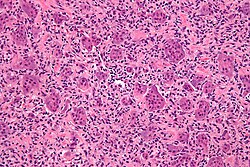

Microscopic

Features:

- Fibrosis.

- +/-Giant cells with round to oval nuclei and nucleoli.[10]

- Bone unaffected by tumour - increased numbers of the following:

- Multinucleated cells (osteoclasts).

- Mononuclear cells around the bony trabeculae (osteoblasts).

DDx:

- Giant cell tumour of bone and other giant cell lesions.

Images

- Brown tumour - intermed mag.jpg

Brown tumour - intermed. mag. (WC)